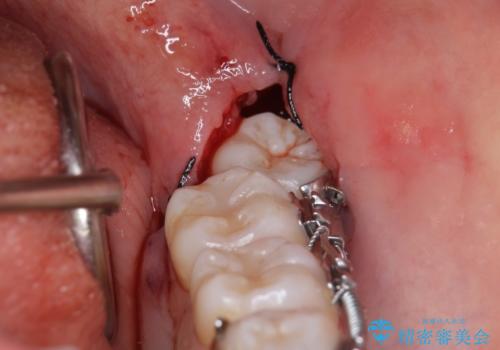

ただし、左下の親知らずを残すには厚みのある歯ぐきを処置しています。(ディスタルウェッジ)

親知らずが歯ぐきに埋まっていると不潔になり、炎症を繰り返すため残しておくことが難しい場合が多いです。

今回は左下の小臼歯を1本抜歯してるのと、手術を行なって親知らずを顎に収めることができました。